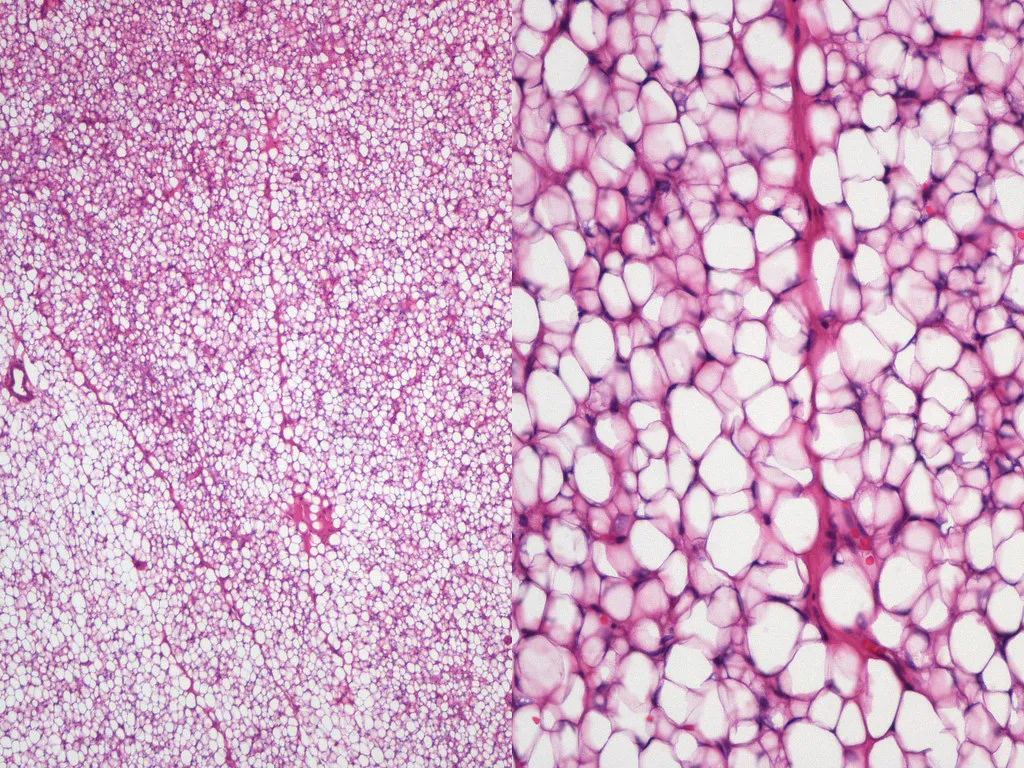

- Histology is key for subtyping:

- Well-differentiated Liposarcoma/ALT: Composed of mature-appearing adipose tissue but with scattered atypical, hyperchromatic stromal cells and fibrous septa. Lipoblasts may be present but are not required for diagnosis if atypia is found.

- Myxoid Liposarcoma: Characterized by a background of myxoid (gelatinous) stroma, a prominent branching capillary network, and small, uniform signet-ring lipoblasts.